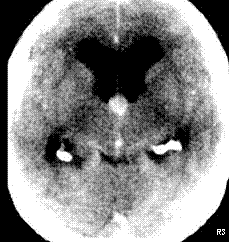

58 year-old with staggering gait and incontinence